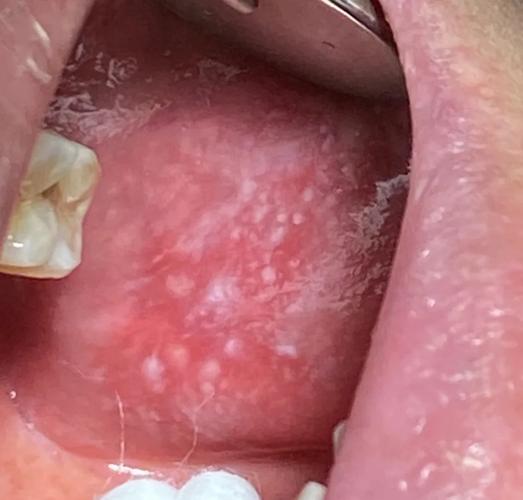

口腔念珠菌病(俗称“鹅口疮”):

- 特点:由真菌(念珠菌)感染引起。

- 表现:通常表现为白色乳凝块状的伪膜,可以擦掉,擦掉后下方有红色糜烂面,在免疫力低下或长期使用抗生素的人群中更常见,严重时会引起黏膜干燥、发红和疼痛。